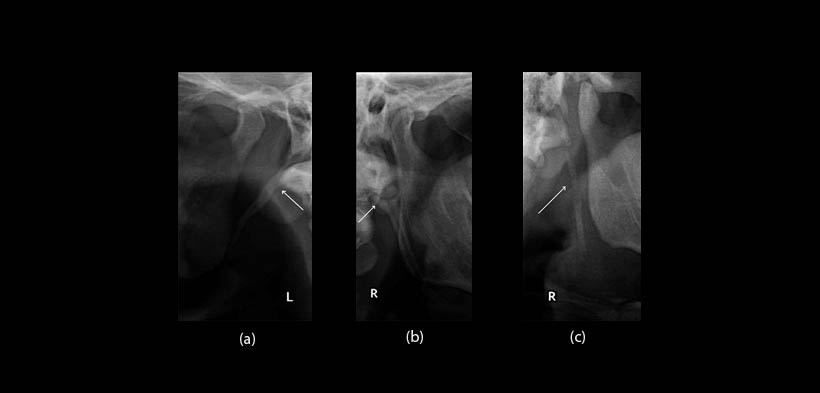

Fig. 4. Clasificación de Langlais et al. (1986). (a) Calcificación de la apófisis estilohioideo alargada (tipo I). (b) Calcificación de la apófisis estilohioideo pseudoarticular (tipo II). (c) Calcificación de la apófisis estilohioideo segmentada (tipo III).